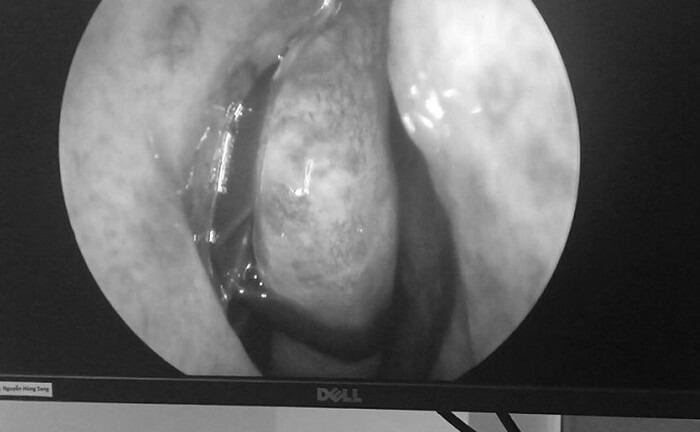

Bác sĩ Phạm Thanh Thúy - Bệnh viện Đa khoa Thu Cúc cho biết, các bác sĩ vừa gắp thành công con vắt sống trong mũi người đàn ông N.H.H., (38 tuổi, ở Hà Nội).